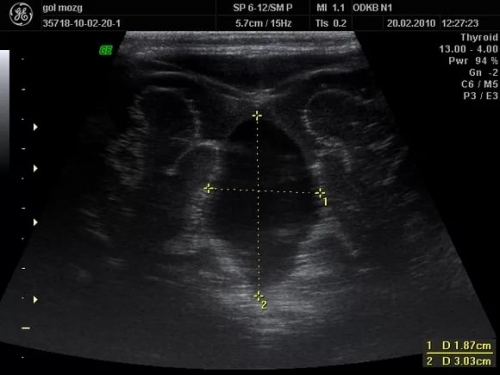

Нейросонография головного мозга новорожденных

Ультразвуковая диагностика, известная также как нейросонография, представляет собой информативный и безопасный способ выявления патологий головного мозга у детей до года.

Сегодня УЗИ головного мозга у новорожденных считается стандартным скрининговым методом и выполняется всем новорожденным для раннего обнаружения возможных отклонений.

Процедура не требует применения анестезии, специальной подготовки и занимает всего 10-12 минут.

Нейросонография грудничков: нормы показателей

В процессе обследования все полученные данные и измерения фиксируются в специальном протоколе.

При этом акцентируется внимание на следующих моментах:

• симметрия правого и левого полушарий;

• четкость извилин и борозд;

• наличие или отсутствие опухолевых образований;

• симметричное строение мозжечка;

• отсутствие свободной жидкости;

• однородность желудочков;

• состояние сосудов;

• аномалии развития.

Как выглядит заключение (норма) УЗИ головного мозга у новорожденного

Безусловно, каждый врач интерпретирует сонограмму по-своему, однако стандартное описание УЗИ головного мозга у новорожденного может выглядеть следующим образом:

Смещения срединных структур отсутствуют, мозговая ткань имеет нормальную эхогенность. Дифференциация структур головного мозга на удовлетворительном уровне, рельеф коры хорошо визуализируется. Структура подкорковых ядер четко выражена. Боковые желудочки находятся в симметричном положении.

Отверстия Монро с обеих сторон проходимы.

Сосудистые сплетения однородные, новообразования не выявлены.

Заключение: без патологий.